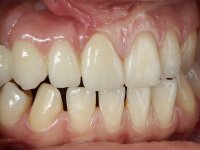

Female patient, 20 years old, non-smoker, had several surgical interventions to correct labial and palatal cleft. Patient presented a significant edentulous area between teeth 13 and 11, also due to the absence of teeth 12 and 15. Due to a traumatic impact, tooth 11 was non-vital, and extensively reconstructed with composite. Patient also had an orthodontic appliance with two prosthetic teeth and a buccal arch in this area to avoid teeth movement in this area. The area of the surgical correction of the labial and palatal cleft presented a significant deformity of hard and soft-tissues.

After the root canal treatment of tooth 11, dental impressions were taken to do a fixed provisional (reinforced) acrylic prosthesis. The provisional bridge included an acrylic component with a gum-shade color, to evaluate the integration of the treatment plan, in relation to function and esthetics. The preparation of teeth 14 and 13 were minimal invasive, with supra-gingival finishing lines, preserving enamel at its uttermost. Tooth 11 was prepared in a conventional way, with an intra-sulcular margin. The provisional bridge was rebased intra-oral with an autopolymerized acrylic. After 4 weeks, a dental impression with a double mixture technique was done. In the dental lab, CAD-CAM technology was used to produce a zirconia framework. In the provisional bridge, it was noted by the patient, and by ourselves, the need for symmetry in the dimensions and shape of the teeth, in relation to their homologues of the 2nd quadrant. Accordingly, a mirror effect was selected in the CAD design of the framework, to mimic in the prosthetic structure the dimensions and shape of the homologous natural teeth. Framework design included also a small zirconia wing covering the palatal surface of the non-prep tooth 21. This wing serves as an additional support and, simultaneously, avoids an eventual occurrence of a future diastema between central incisors. Color selection of teeth and soft-tissues was done by the ceramist in the dental office. After evaluation and approval of the prosthetic work placed in mouth, the dental bridge was bonded. This bonding procedure was optimized by the addition of a zirconia liner in the inner surface of the framework and in the internal surface of the wing. This treatment proved to be esthetically acceptable and functionally able, with a strong contribution to the patient’s self-esteem.